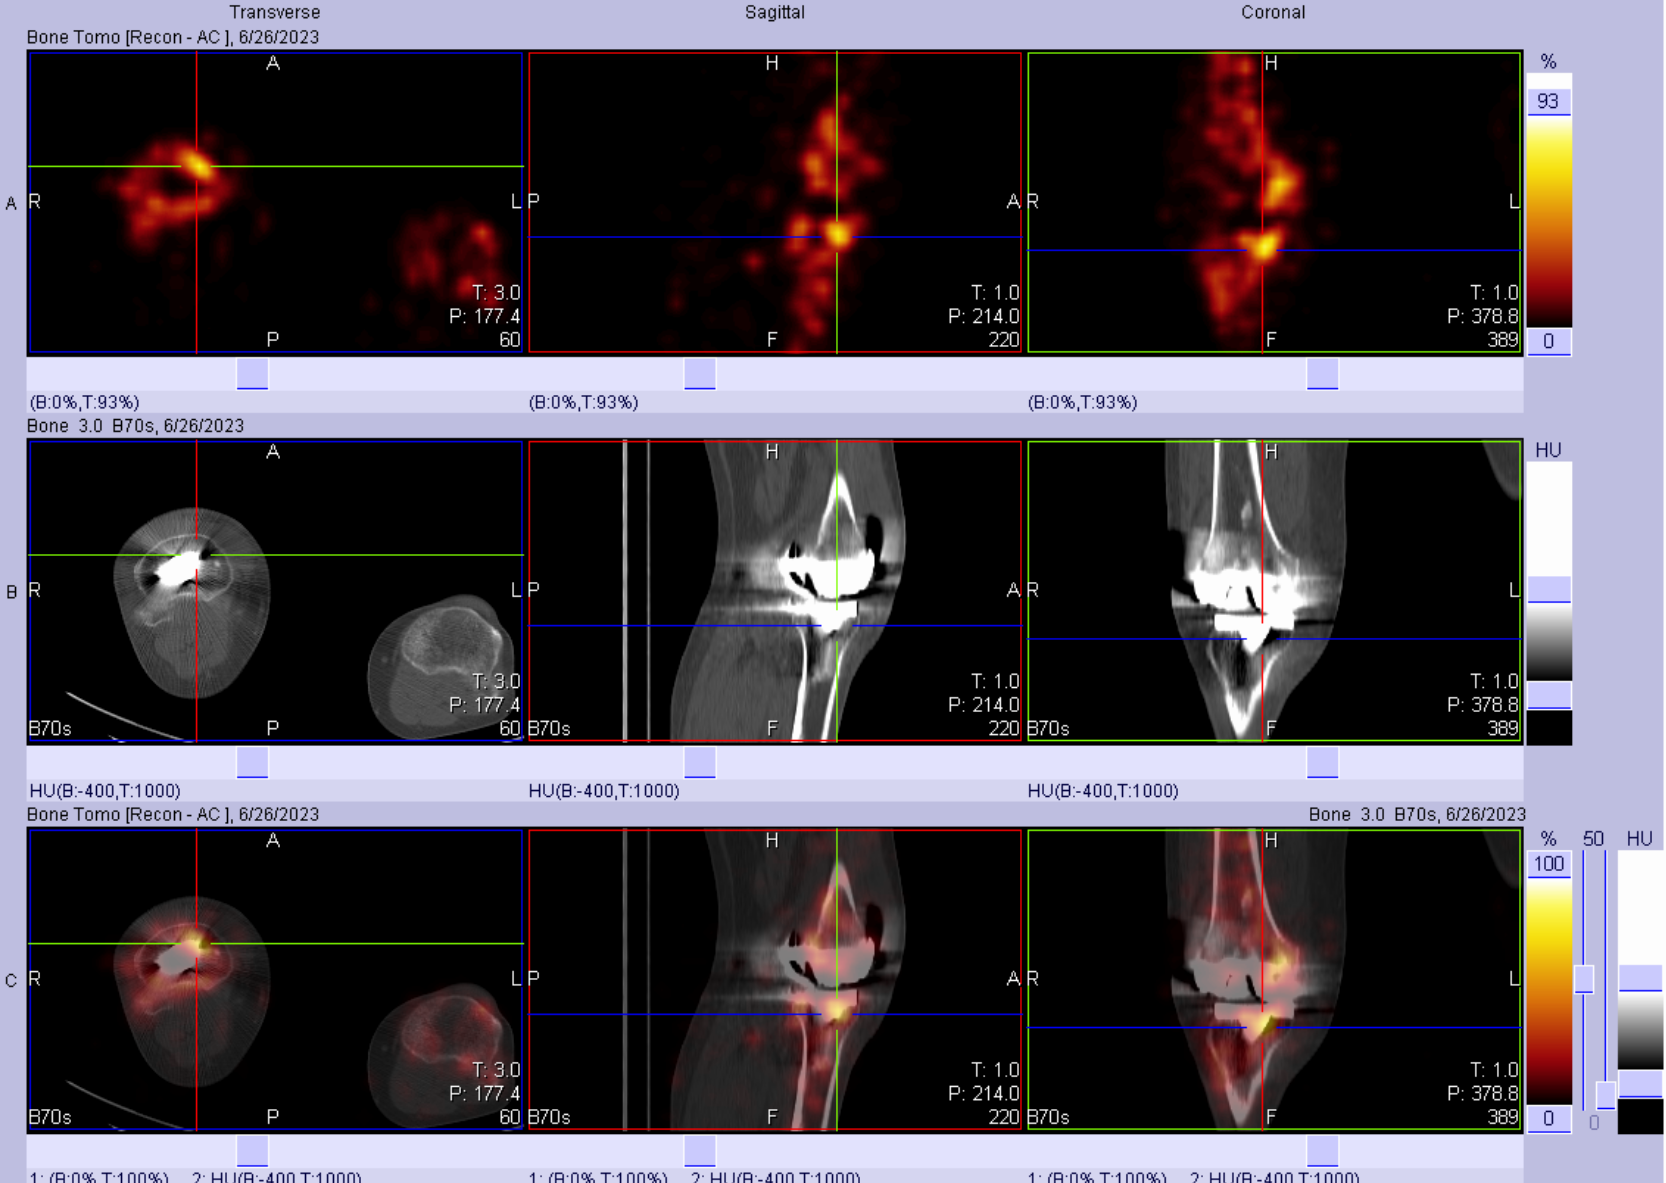

女性患者,1年前因“右膝关节炎”于当地医院行“右侧人工膝关节置换”手术治疗,术后康复良好。6个月前患者右膝关节疼痛、肿胀,于当地医院给予抗感染治疗,治疗后无明显好转,近期患者自觉症状持续加重,于我院就诊。入院后完善相关化验检查,血常规、C反应蛋白及血沉未见明显异常。

三相骨显像结果提示:右侧膝关节置换术后,三相骨显像血流相、血池相及延迟相均阳性,结合影像学特征考虑存在感染。

患者后续行手术治疗,术中见假体外侧脓性苔藓浸泡,培养出近平滑假丝酵母。

除上述三相之外,吉大二院核医学科还免费为患者完善同机低剂量CT扫描,并利用软件功能进行SPECT与CT的同机融合,实现对解剖结构细节的展现,提供更为准确、详细的诊断信息,实现功能代谢显像与CT解剖显像的实时融合,更有利于对病变性质进行分析。

①假体周围感染:典型表现为血流相、血池相、延迟相显像剂明显异常浓聚、范围广且弥漫,同机CT常可见软组织影、骨质破坏等影像。